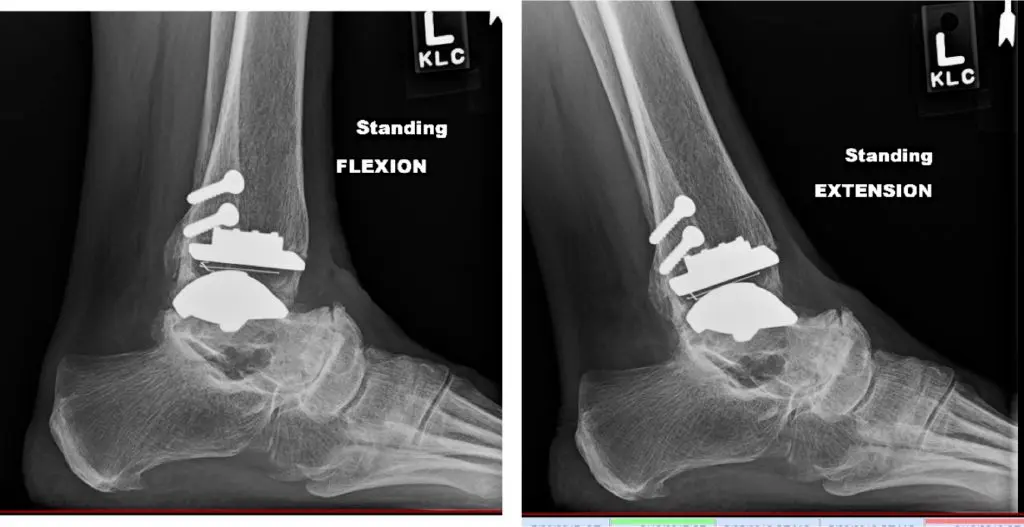

“The goals of ankle replacement surgery are to maintain or

improve range of motion, and to restore alignment and stability,” says Park. “In

addition, we believe ankle replacement restores a more natural gait compared to

ankle fusion.”

Outcome: full recovery with pain resolution and restoration of ankle motion